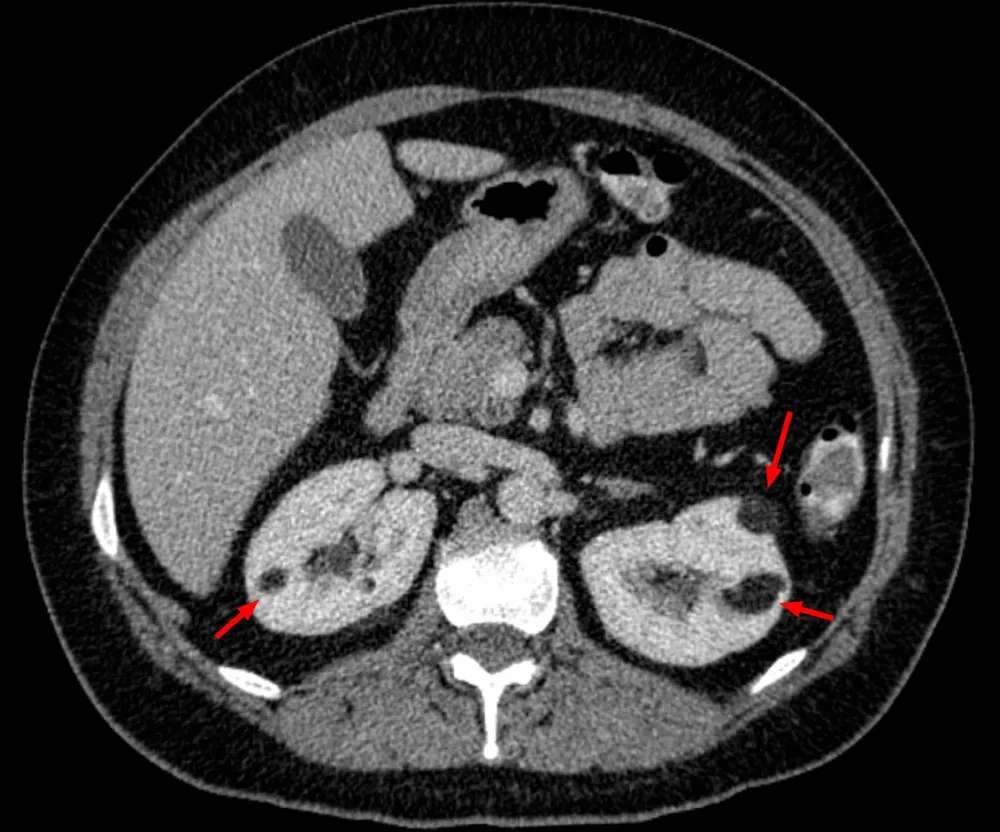

Febre e dor no flanco: pielonefrite ou infarto renal? Saiba como identificar os sinais radiológicos que fazem a diferença no diagnóstico e garantem o tratamento correto!

Valkercyo Feitosa

2 anos atrás